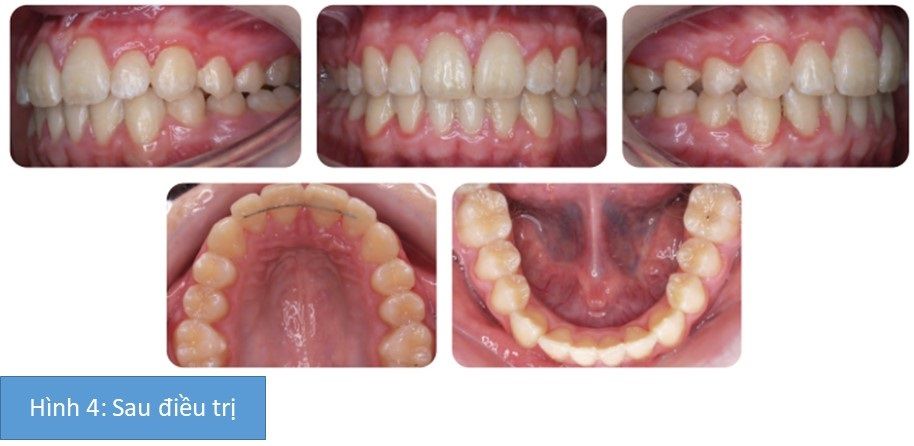

- Đeo hàm duy trì vĩnh viễn như hình 4

Kết quả cuối cùng hình 4.